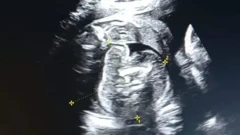

Mucjisada lagu arkay ilmo ku dhex jira caloosha hooyo xaamilo ah iyo waxa lagu soo dhex arkay caloosha ilmahaas